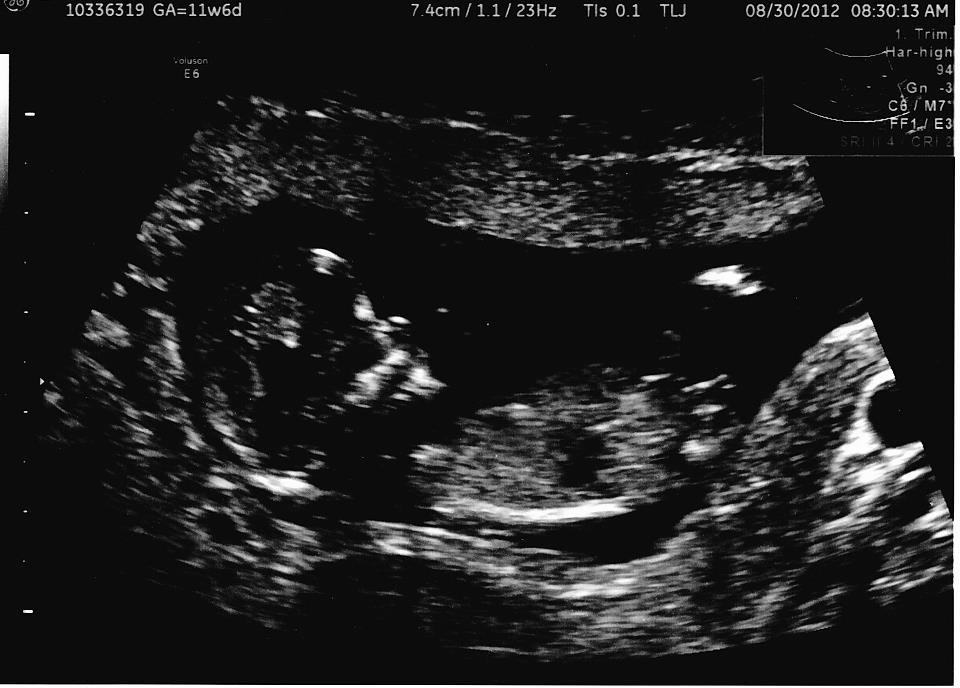

11 weeks and 6 days here. What do you think??

If what I'm seeing is a nub...my guess is girl!

I say girl too!

Boy

Hard one, but I'm gonna say girl.

early shot, but thinking girl. If this was at 13 or 14 weeks I would give a very confident girl guess.

It's a GIRL!!